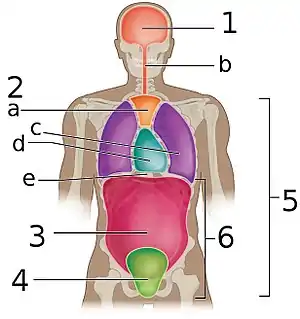

The various cavities of the human body as seen in a frontal projection, with the pelvic cavity labeled 4. | |

The pelvic cavity is a body cavity that is bounded by the bones of the pelvis. Its oblique roof is the pelvic inlet (the superior opening of the pelvis). Its lower boundary is the pelvic floor.

The pelvic cavity primarily contains the reproductive organs, urinary bladder, distal ureters, proximal urethra, terminal sigmoid colon, rectum, and anal canal. In females, the uterus, fallopian tubes, ovaries and upper vagina occupy the area between the other viscera.[1][2]

The rectum is located at the back of the pelvis, in the curve of the sacrum and coccyx; the bladder is in front, behind the pubic symphysis. The pelvic cavity also contains major arteries, veins, muscles, and nerves. These structures coexist in a crowded space, and disorders of one pelvic component may impact upon another; for example, constipation may overload the rectum and compress the urinary bladder, or childbirth might damage the pudendal nerves and later lead to anal weakness.